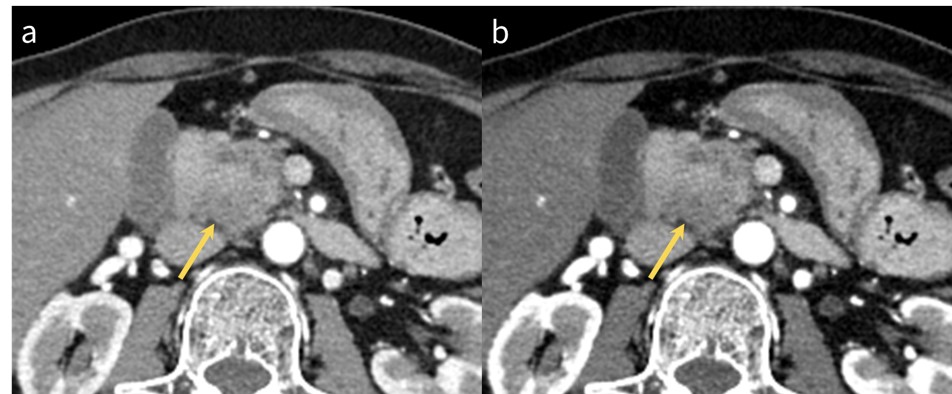

RevolutionApexElite_Gifu02_05.jpg

図4 仮想単純画像

a: 真の単純画像

b: 仮想単純画像

肝内脈管にわずかな造影剤濃度が残存しているが 、

全体としてはヨードがきれいに差し引かれた単純CT画像が作成でき、真の単純CT画像に置き換えが可能だ。